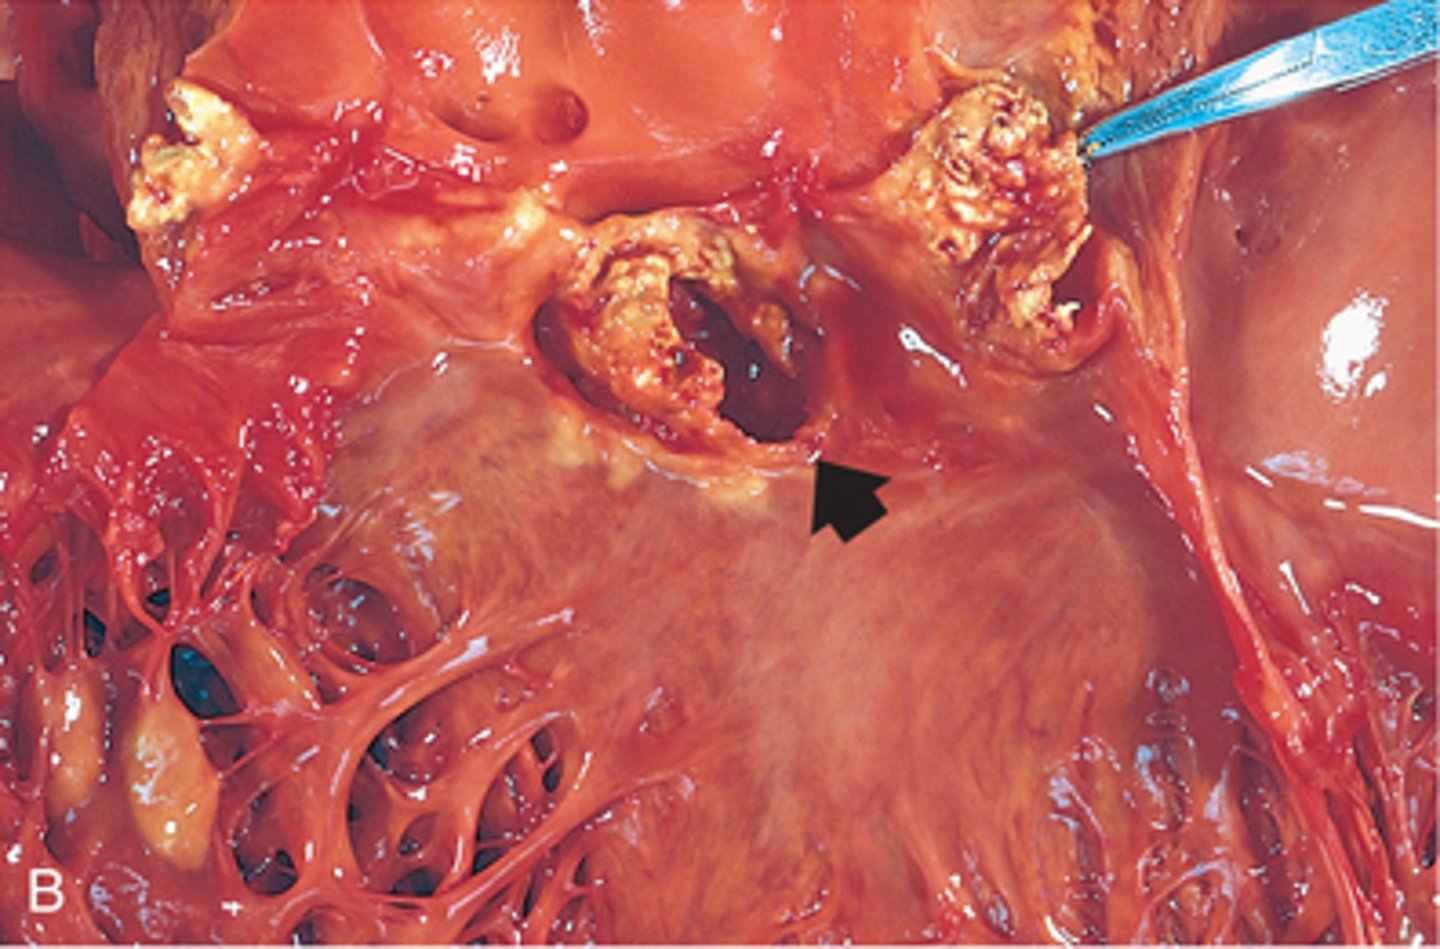

Infective Endocarditis

Pathogen: Staphylococcus aureus, Streptococcus pyogenes

S+S: "Vegetations" on the endocardium, fever, heart murmurs, myalgia, Osler's nodes, Janeway's lesions

Transmission: Entry of bacteria into the bloodstream following tooth brushing, oral surgery, phlebotomy, IV, injections